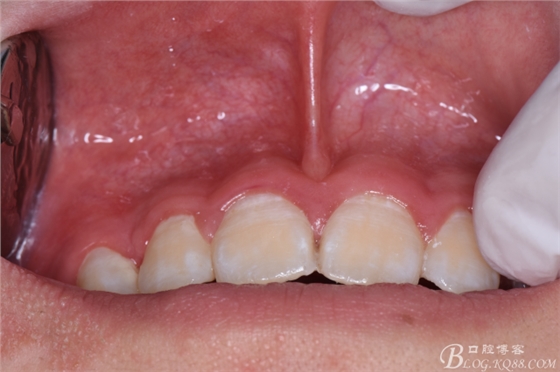

圖5.唇側(cè)未能捫及明顯隆起,考慮手術(shù)的課操作性及視野清楚,結(jié)合cbct,從唇側(cè)前庭溝處做弧形切口